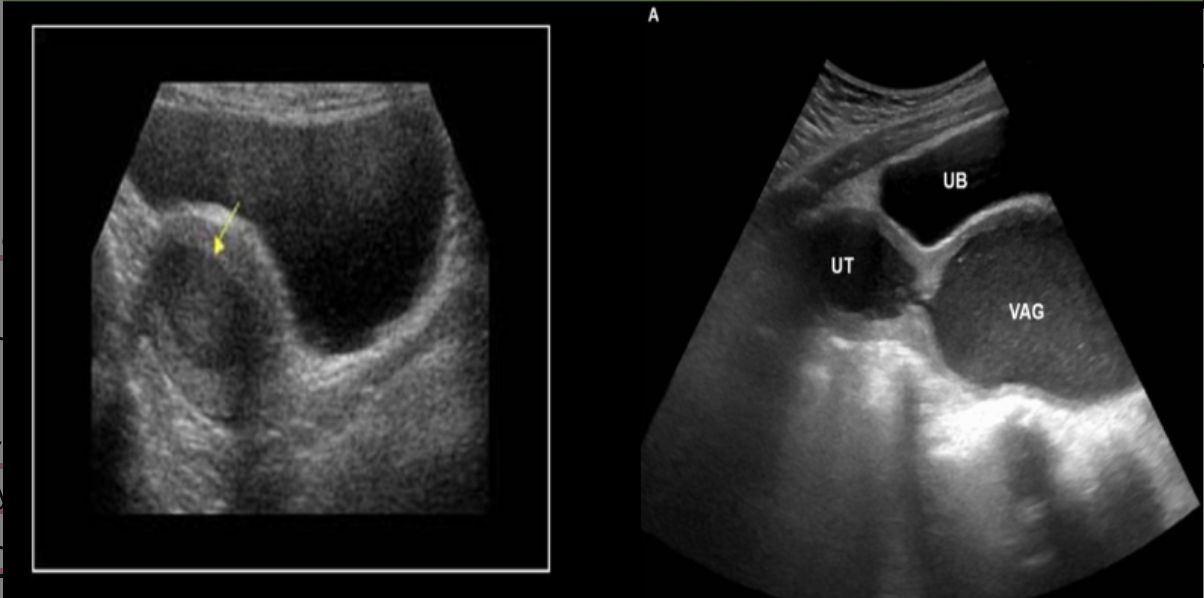

which congenital abn is this

a) uterine subseptus

b) uterine bicornis bicollis

c) uterine arcuatus

d) uterine bicornis unicollis